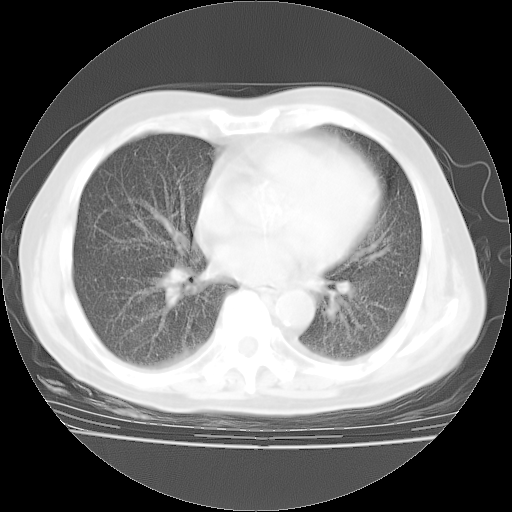

4月28日肺部CT——再次出现类似去年5月9日——磨玻璃样、间有“粟粒样”改变。

1、108#的是4月14日的胸部CT(发此贴时还没看着28日的CT)。14日的胸部CT其实已经出现改变(如108#所述),个人认为28日的胸部CT除纵膈窗疑似有双侧胸膜增厚或少量胸积液(可行胸部B超明确)外,与4月14日对照病变有所加重;2、已经给予“异烟肼、利福平、乙胺丁醇”抗痨治疗?如果是,甲强龙80mg可缓慢减量;如果环磷酰胺已停用,暂不使用;3、中性粒细胞92%,明显升高,目前体温情况?注意合并细菌感染可能,使用左氧氟沙星情况下,是否联用B-内酰胺类抗菌药物?另外是查免疫全套非风湿全套。